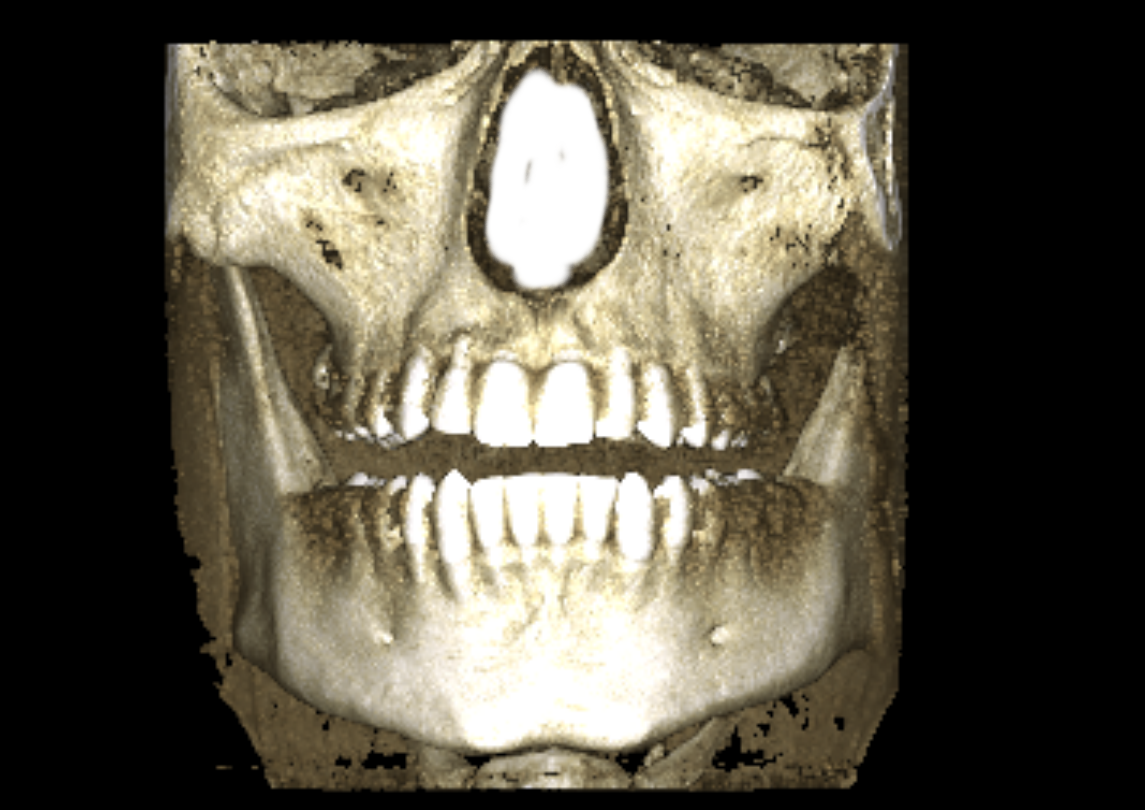

you can also see that my alveolar bone is short af vertically which causes lot of issues like lack of upper teeth show and small root on the teeth. in particularry my right incisor is hanging off by a thread:feelswah:

Dude first, you are right I just saw how fucked up that root was(still is), also seems like you have a permanent retainer on top, I wonder, you got this xray cbct or whatever the fuck this is called, because of a doctor's suggestion or on your own? like did a professional give you rough advice yet, also, you are right to be worried I mean I have seen jawhacks' "over-expanded" expander like 82+turns, and saw how fcked up the roots were, but it can be saved you are not fucked over yet, but I fear for you brother, and that's a rare thing lol, do whatever you can to get it right and fckin rot in orthodontic knowlage if you have to if that means you can debate your doctor or confirm for yourself that what he says is valid and not unnecessary

you cant see the roots there properly, here let me show you:

wtf this looks even worse, if I hadn't seen the poorly edited correction you made in the image I'd assume this is edite, how the fck do you get this result? I mean more power to you, prob getting a full implant at early 30s xd and the funny thing is that the implant most likely will be better